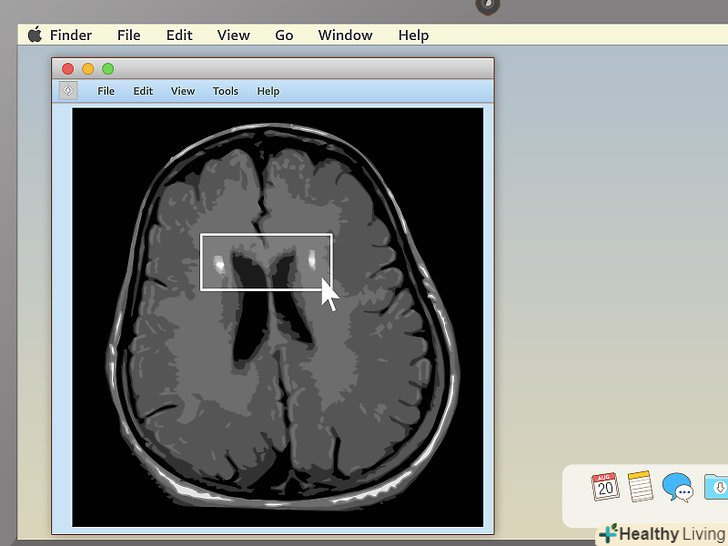

Використовуйте горизонтальну проекцію при перегляді МРТ мозку.МРТ тканин мозку використовується для діагностики пухлин мозку, нагноєнь та інших захворювань мозку. Найпростіше розглянути їх в горизонтальній проекції, спускаючись зверху вниз. Шукайте несиметричні ділянки. Світле або темна пляма, якого немає з іншого боку, може стати причиною для занепокоєння.- Пухлини мозку зазвичай являють собою круглі освіти у формі м'яча для гольфу. На МРТ вони відображаються як дуже світлі або сірі області, оточені білим кільцем.[8] однак і інші захворювання (наприклад, множинні ущільнення) відображаються як білі ділянки, тому лише одне це не може вказувати на пухлину мозку.[9]